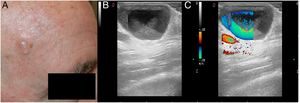

CASO 2: el segundo caso fue un hombre de 72 años con un nódulo translúcido en la sien derecha (fig. 3). El diagnóstico clínico era sugestivo de un hidrocistoma. En la exploración ecográfica también observamos una lesión quística hipoecoica con un flujo turbulento en el Doppler color (fig. 4). El diagnóstico anatomopatológico final fue consistente con el diagnóstico clínico de hidrocistoma.

Chin et al. evaluaron varios hidrocistomas empleando US. Sugirieron que dichas estructuras mostraban una lesión quística con una superficie hiperecoica y un centro hipoecoico (restos de lipofuscina) o un centro ecolúcido (líquido claro)3. Perez-Lopez et al. insistieron en la ausencia de flujo dentro de estas estructuras4. Sin embargo, en nuestros casos hemos visto que a veces estas estructuras pueden mostrar una señal Doppler positiva.

En nuestros casos, el movimiento del material en el interior del hidrocistoma condujo a una imagen en el Doppler color que puede interpretarse incorrectamente como flujo vascular.